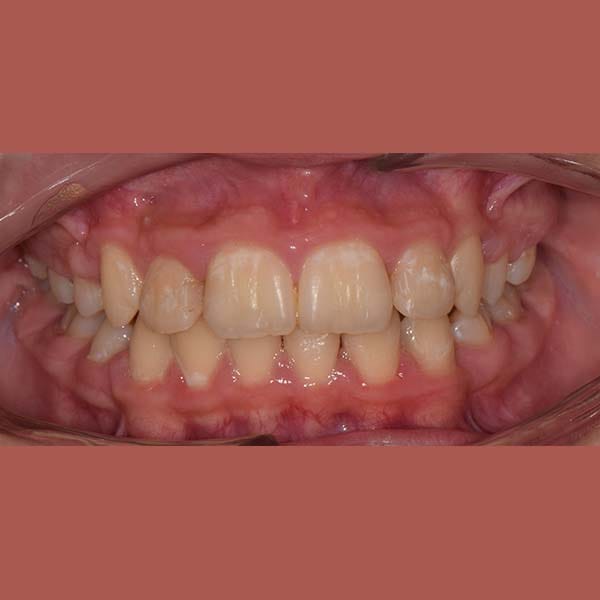

AFTER

This young woman suffered from an upper jaw stenosis, crowded teeth, and the absence of one of the upper molars.

She was treated with Daimon braces (an orthodontic device that doesn’t require rubber to fix the archwires, which reduces friction and speeds up treatment).

At the end of the treatment, we were able to see a clear expansion in her upper jaw, her teeth were aligned beautifully, and the gap resulting from the absence of the molar was closed orthodontically.